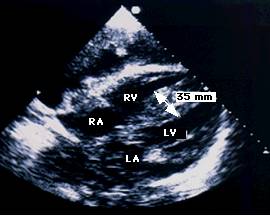

Ecocardiografia permite evaluarea afectarii functiei contractile, excluderea unor boli valvulare sau pericardice. Se apreciaza forma si functia VS (tipic VS globulos cu functie contractila global alterata), gradul insuficientelor valvulare, prezenta trombozei intracavitare (intraatriala sau intraventriculara). Cresterea dimensiunilor cavitatilor stangi si drepte este progresiva cu cresterea clasei functionale NYHA. Producerea emboliilor se asociaza cu dimensiunea VS si fractia de ejectie (FE).

Confirma diagnosticul de CMH, cuantifica elementele morfologice - distributia hipertrofiei, functionale - hipercontractilitatea VS si hemodinamice - gradientul intraventricular.

Examenul Doppler evidentiaza prezenta gradientului, a insuficientei mitrale si anomaliile functiei diastolice.